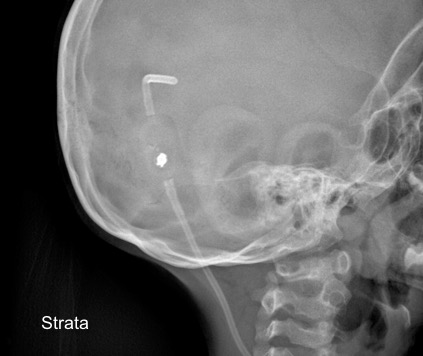

il existe un grand nombre de valves ; il n’est pas toujours aisé de les reconnaitre radiologiquement. voici la liste des plus courantes :

comment reconnaitre radiologiquement le type de valve ?

il est important pour le radiologue qui fait une IRM quel est le type de valve en raison des implications sur l’image et sur le fonctionnement de la valve (en pratique ce surtout les anciennes sophysas ancien modèle qui se dérèglent dans l’IRM).